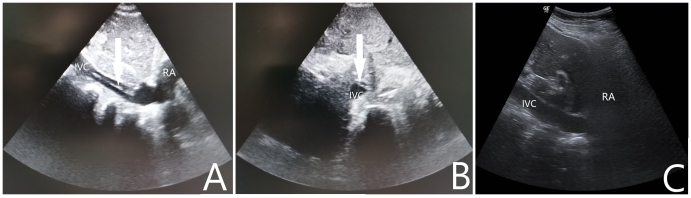

病例2:女性,69岁,农民,既往有“高血压病”“脑梗塞”“痛风”史,长期服用氨氯地平片及氯吡格雷片。主诉“胸闷胸痛2 h”于2021-10-27入院。入急诊查心电图提示存在“高侧壁、前臂、前侧壁ST段弓背向上抬高”,在送往介入室的途中出现意识不清,大动脉搏动消失,予以胸外按压、气管插管等高级生命支持。复苏期间心电监护提示室速、室颤,予以多次电除颤无法维持ROSC,征得家属同意后行ECMO支持,ECMO参数设定:转速3 400 r/min,流速3.5 L/min,吸入氧浓度100%,气流量4 L/min,成功转机后停止胸外按压,患者出现ROSC,复查床旁心电图提示“高侧壁、前臂、前侧壁ST段较前抬高”。患者出现ROSC后转运至介入室行经皮冠脉造影提示左前降支近中段次全闭,予行冠状动脉造影术+ 冠状动脉成形术+ 药物洗脱冠状动脉支架植入术+ 主动脉球囊反博泵置入,术前ECMO上机后使用肝素4 500 U,入导管室测ACT 185 s,术中追加肝素1 000 U。返回急诊ICU后给予全身肝素化抗凝,每2 h监测一次APTT,目标APTT维持在60~80 s。入院当天查心脏彩超提示LVEF:20%,左室壁运动明显减弱;入院后第1天患者口鼻腔、穿刺处大量渗血及皮下血肿,血红蛋白进行性下降,给予输红细胞悬液6 U、新鲜冰冻血浆1 000 mL并调整肝素抗凝强度使得APTT维持在50~60 s。入院后第4天复查心脏彩超提示LVEF:55%,心肌活动较前好转,并已脱离血管活性药物,遂撤除ECMO,撤机前ECMO参数设定:转速2 300 r/min,流速2.0 L/min,吸入氧浓度50%,气流量3 L/min。在拔除ECMO导管后即刻行超声筛查发现下腔静脉至右心房入口有血栓形成,长约7.2 cm,宽0.4 cm,随血流飘动(如图 2A、2B所示),筛查下肢其他部位未见明显血栓形成,遂给予依诺肝素钠100 IU/kg皮下注射每12 h一次治疗。入院后第5天行超声检查下腔静脉未见明显异常回声(如图 2C所示)。住院期间患者未出现过下腔静脉综合征或肺栓塞的症状或体征。入院后第8天患者转心内科病房,康复后出院随访1个月未遗留任何中枢神经系统并发症。

| A:下腔静脉纵向超声扫描显示下腔静脉至右心房入口有血栓形成;B:下腔静脉水平超声扫描显示下腔静脉内漂浮的血栓影;C:经治疗后超声在下腔静脉未见明显异常回声;RA:右心房,IVC:下腔静脉 图 2 撤离ECMO后即刻行下腔静脉超声检查 |